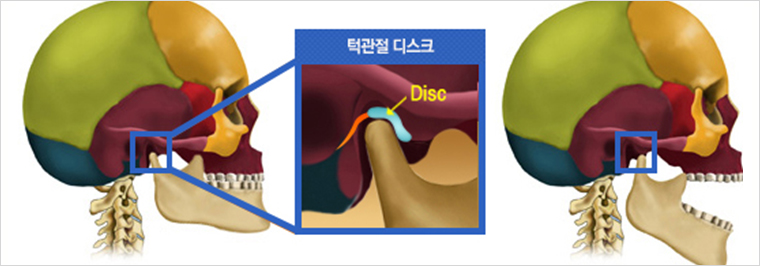

턱관절장애란?

턱을 둘러싼 근육-뼈-관절의 배열이 틀어지거나 턱관절을 감싸는 근육, 연골, 관절 디스크 등이 손상되면 입을 잘 벌리지 못하거나 입을 벌릴 때마다 턱관절에서 딱딱 소리가 나는 증상이 나타납니다. 턱뼈와 이어진 얼굴과 목의 근육이 긴장되므로 두통과 목의 통증이 동반되는 경우가 흔하며 손상된 쪽의 턱관절이 잘 열리지 않아 안면비대칭으로 진행되는 경우도 많습니다. 이러한 증상을 통칭하여 ‘턱관절장애’라고 합니다.

턱관절장애 유형

턱관절 디스크가 정상위치보다 앞으로 나와있는 상태입니다. 얼굴뼈와 턱뼈 사이에서 윤활작용을 해야 할 디스크가 앞으로 빠져있기 때문에 입이 잘 벌어지지 않고 입을 벌릴 때 통증을 느끼게 됩니다. 입을 크게 열면 앞으로 빠져있던 디스크가 턱뼈에 걸려 제자리로 돌아가며 ‘딱’하고 소리가 나는 경우와 입을 아무리 벌려도 디스크가 제자리로 돌아가지 못해 소리조차 나지 않는 경우로 나눌 수 있습니다. 얼굴의 근육과 인대 손상은 물론 목의 이상까지 동반하는 경우가 많기 때문에 수개월 이상의 치료가 필요한 경우가 대부분입니다.

턱근육과 인대 손상 뿐만 아니라 턱관절에 관절염이 생긴 상태입니다. 외상 또는 기타 다른 이유로 턱관절 자체에 변형이 생기는 경우도 있습니다. 단순 관절염증의 경우 치료가 잘되는 경우가 많지만, 관절 자체의 변형이 심한 경우, 수술이 필요한 경우도 있습니다.

-

관절염

-

관절변형